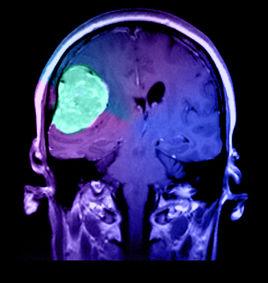

核磁共振成像

核磁共振成像(英語:Nuclear Magnetic Resonance Imaging,簡稱NMRI),又稱自旋成像(英語:spin imaging),也稱磁共振成像(Magnetic Resonance Imaging,簡稱MRI),台灣又稱磁振造影,香港又稱磁力共振成像,是利用核磁共振(nuclear magnetic resonance,簡稱NMR)原理,依據所釋放的能量在物質內部不同結構環境中不同的衰減,通過外加梯度磁場檢測所發射出的電磁波,即可得知構成這一物體原子核的位置和種類,據此可以繪製成物體內部的結構圖像。將這種技術用於人體內部結構的成像,就產生出一種革命性的醫學診斷工具。快速變化的梯度磁場的套用,大大加快了核磁共振成像的速度,使該技術在臨床診斷、科學研究的套用成為現實,極大地推動了醫學、神經生理學和認知神經科學的迅速發展。